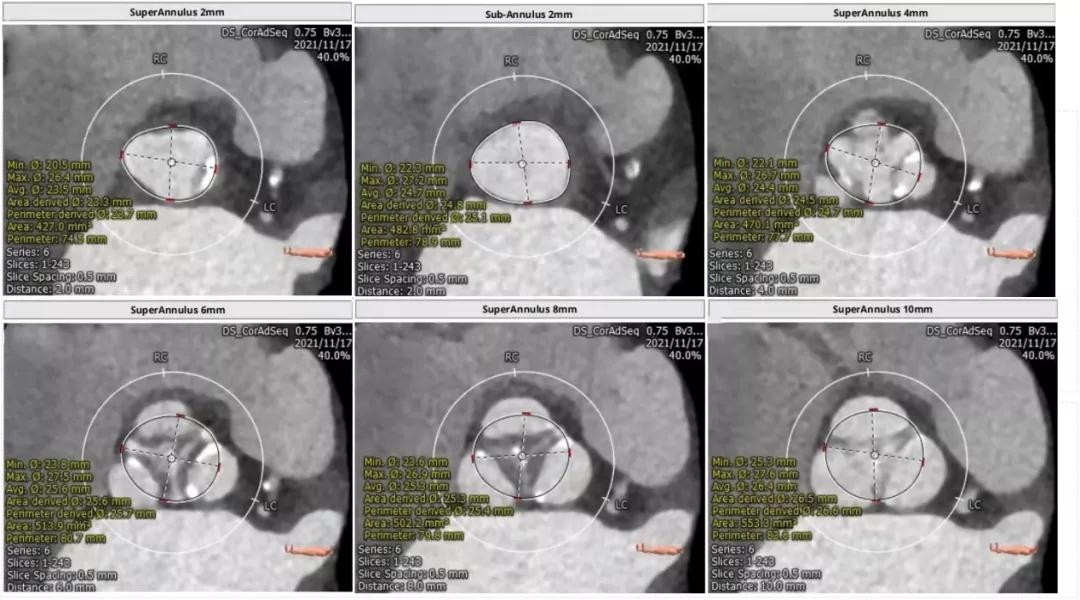

主动脉瓣CT评估:

三叶瓣,瓣环直径22.4mm,瓣环长短径分别为25.0*20.0mm,周长为70.4mm,面积为383.4mm²。左室流出道直径21.8mm,瓦式窦31.7mm*30.2mm*30.6mm,左冠高度11.1mm,右冠高度15.3mm,窦管交界直径26.3mm。

瓣上多平面测量:

根部解剖:

主动脉瓣CT评估:三叶瓣,瓣环直径24.2mm,瓣环长短径分别为26.5*21.1mm,周长为75.5mm,面积为436.8mm²。左室流出道直径25.4mm,瓦式窦30.4mm*34.4mm*33.2mm,左冠高度13.8mm,右冠高度16.6mm,窦管交界直径30.3mm。